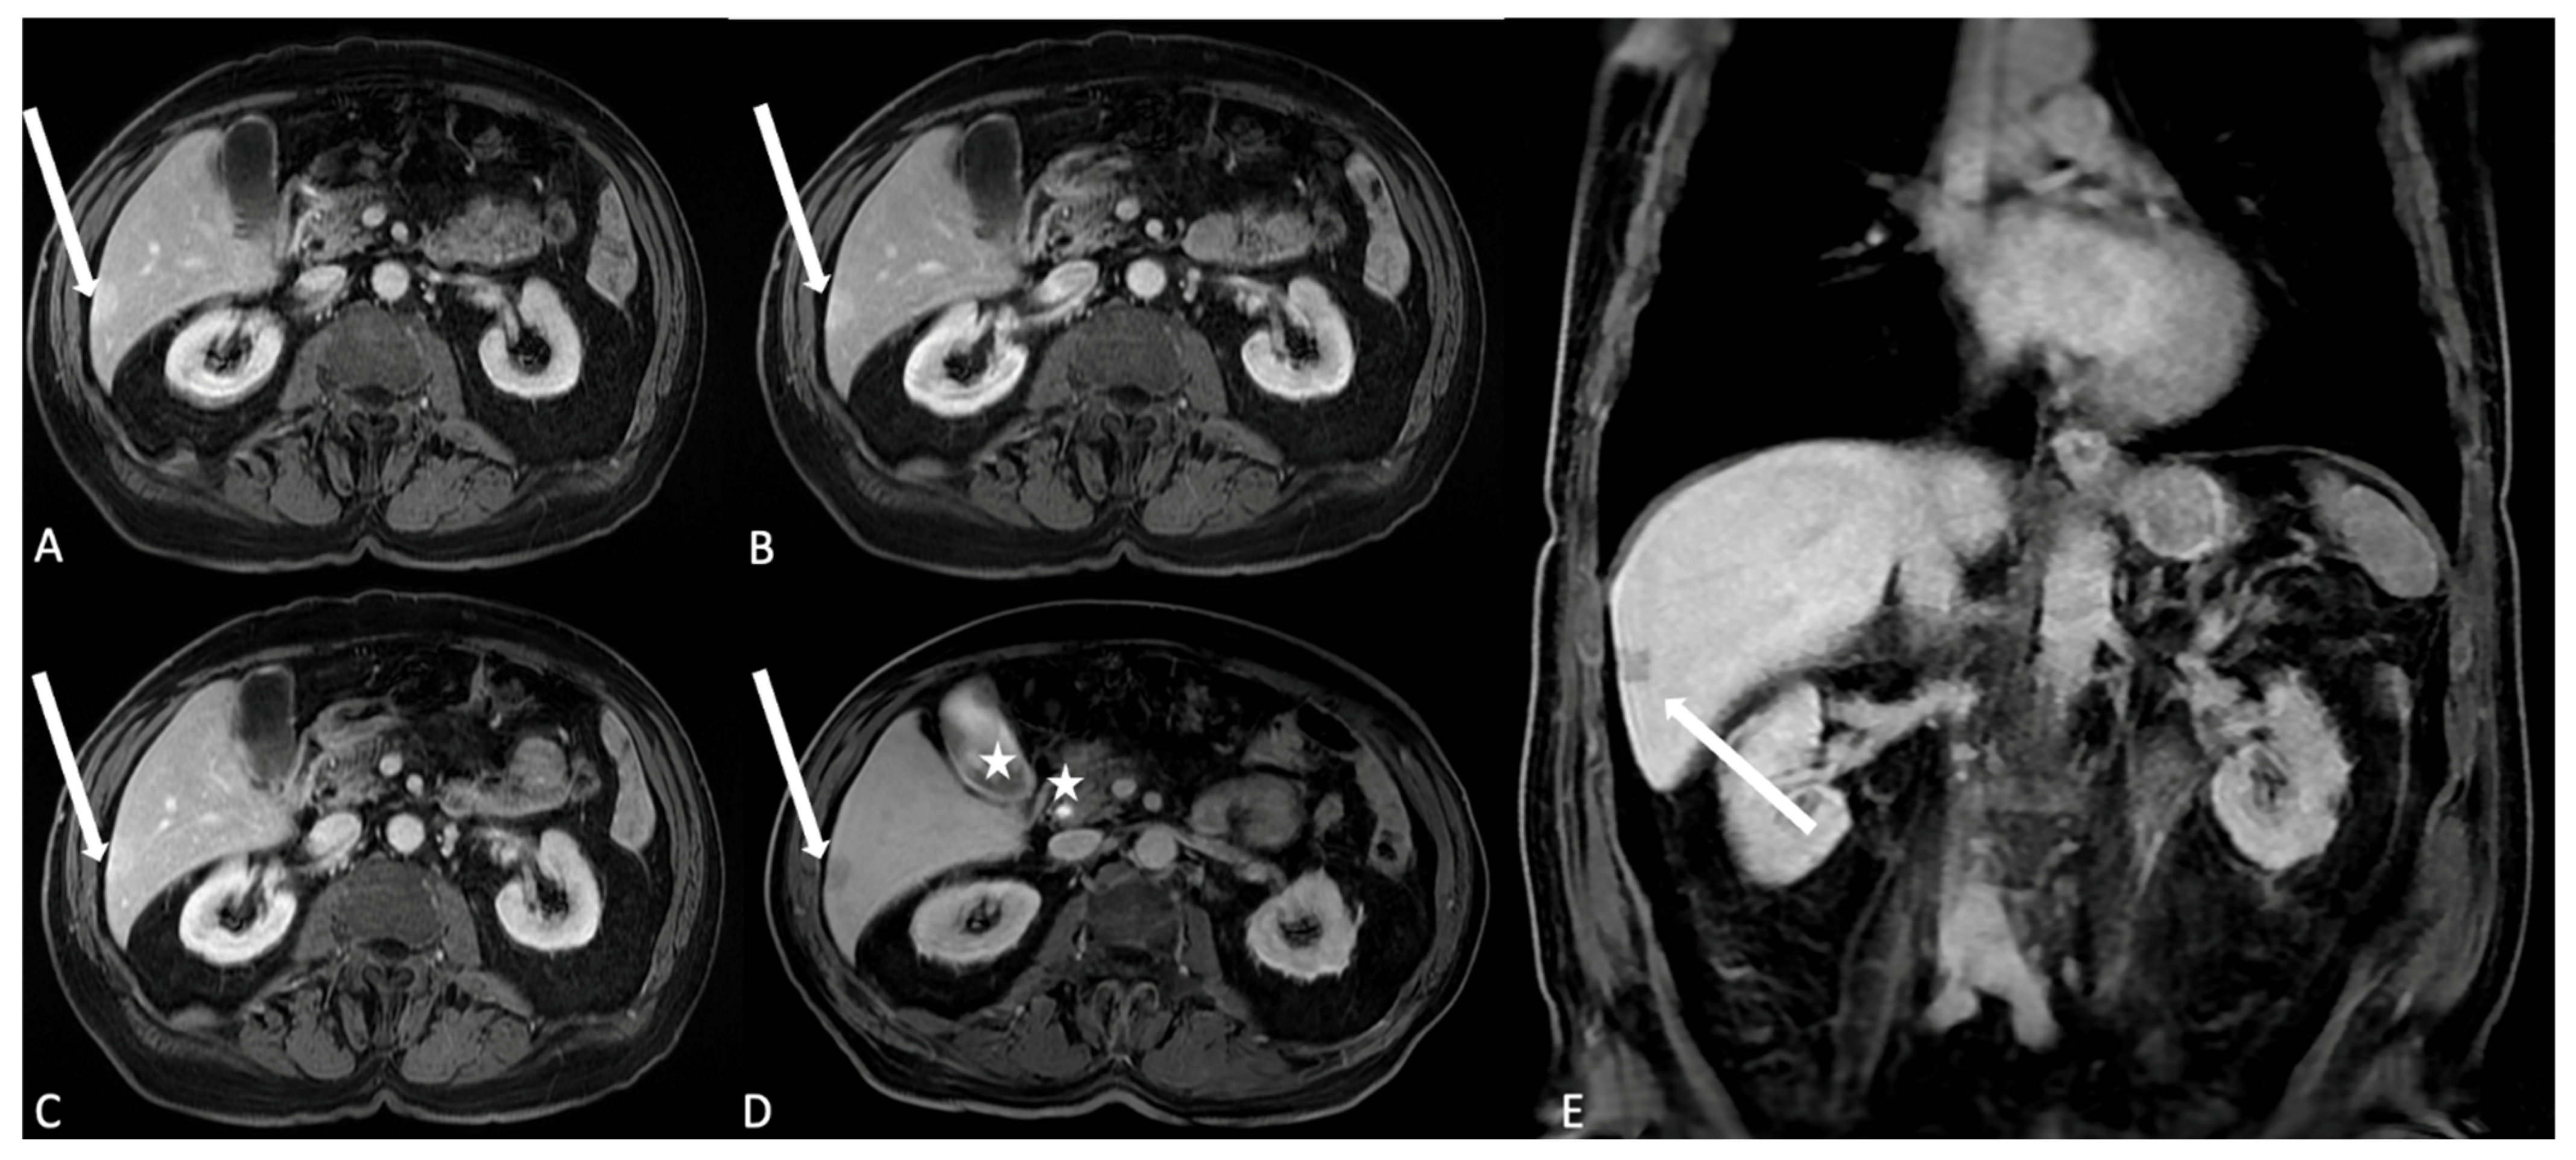

Figure 5. T1 LAVA axial images after HSCA (gadobenate dimeglumine) intravenous administration. (A) The arterial phase. Arterial structures and hypervascular lesions are evidenced: in the liver segment 6, it is possible to identify a subcapsular hyperintense area as indication of a hypervascular behavior (arrow); (B) in the venous phase, the liver parenchyma reach the best enhancement and the hypervascular area in segment 6 shows persistent enhancement (arrow); (C) the delayed/equilibrium phase allows representation of interstitial and extracellular spaces enhancement. The subcapsular lesion is quite completely homogeneous to the liver parenchyma arrow, suggesting the angiomatous nature of the lesion. (D,E) Axial and coronal images after HSCA (Multihance) intravenous administration of the same patient acquired in the delayed hepatobiliary phase show the opacification of the gallbladder lumen and the choledocic duct (stars); the subcapsular lesion is also identified as the hypointense area (arrows), confirming the vascular nature of the angioma and the lack of hepatocyte uptake and biliary excretion.